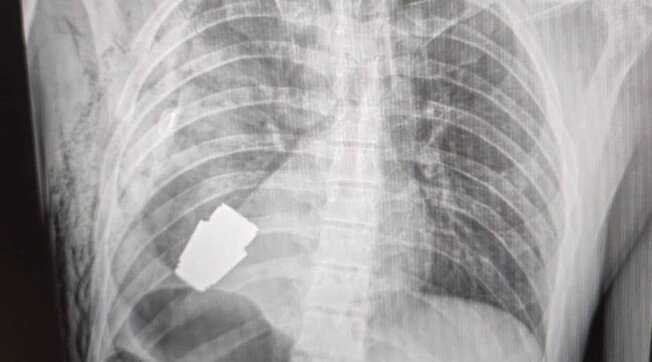

KYIV. Un soldato ucraino è stato operato con successo a Kyiv per la rimozione di una granata inesplosa dal petto, un intervento destinato a finire nei libri di testo di medicina. Il chirurgo ha estratto l’ordigno da appena sotto il cuore del militare. La vice ministra della Difesa ucraina, Hanna Maliar, in un post sui social ha mostrato la foto della radiografia che ritrae la granata all’interno del corpo del soldato e fa sapere che “i medici militari hanno effettuato un'operazione per rimuovere una granata Vog, che non è esplosa, dal corpo del soldato”, continua, “l’operazione è stata eseguita senza utilizzare l'elettrocoagulazione, un metodo comune per controllare il sanguinamento durante l'intervento chirurgico, perché la granata poteva esplodere in qualsiasi momento".

Anton Gerashchenko, consigliere ministeriale per gli affari interni dell’Ucraina, in un comunicato su Telegram dice che “la parte inesplosa della granata è stata prelevata da sotto il cuore. La granata non è saltata in aria, ma è rimasta esplosiva”.